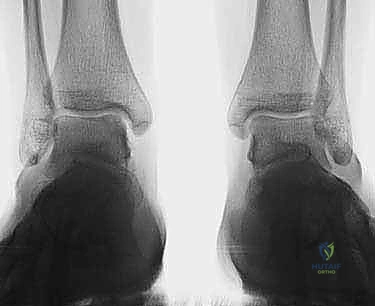

2. التصوير الطبي المتقدم

بما أن الغضاريف لا تظهر بوضوح في الأشعة العادية، يعتمد التشخيص النهائي على تقنيات التصوير المتقدمة:

- الأشعة السينية (X-rays): تُستخدم كخطوة أولى لاستبعاد الكسور العظمية الكبيرة والتهاب المفاصل المتقدم. في بعض الأحيان، يمكن رؤية "ظل" أو كيس عظمي يشير إلى وجود آفة.

- التصوير بالرنين المغناطيسي (MRI): هو المعيار الذهبي (Gold Standard) لتشخيص OLTs. يُظهر الرنين المغناطيسي الغضروف بدقة عالية، ويحدد حجم الآفة، عمقها، وحالة العظم تحت الغضروفي (مثل وجود وذمة عظمية - Bone Marrow Edema).

- الأشعة المقطعية (CT Scan): يطلبها الدكتور هطيف أحياناً للحصول على خريطة ثلاثية الأبعاد دقيقة للعظم، مما يساعد في التخطيط الجراحي وتحديد حجم الرقعة العظمية المطلوبة للزرع.